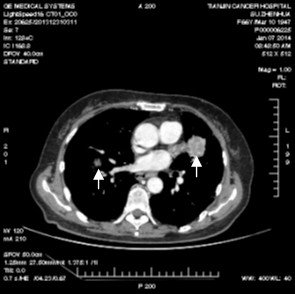

安罗替尼是一种作用于肿瘤细胞内多个靶点的抗癌新药,可通过诱导细胞凋亡杀死主要肿瘤,还可通过抑制肿瘤新生血管生成、断绝其营养供应而“饿死”残余肿瘤。由于其独特的抗癌机制,其对已抗拒传统药物的肿瘤细胞仍可能有效、从而为接受三线及以上治疗的患者带来了希望。在目前进行的试验中,一例有双肺转移、已经历六种治疗、肿瘤依然进展的患者在安罗替尼治疗三周后双肺病灶缩小累积接近50%,取得了既往治疗未达到过的效果。

治疗后肿瘤明显缩小(箭头所示)